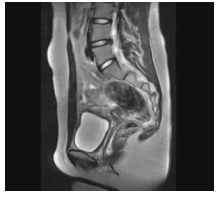

A imagem a seguir representa

A

TC de pelve feminina.

B

TC de pelve masculina.

C

RM de pelve masculina.

D

TC de pelve feminina com feto.

E

RM de pelve feminina.